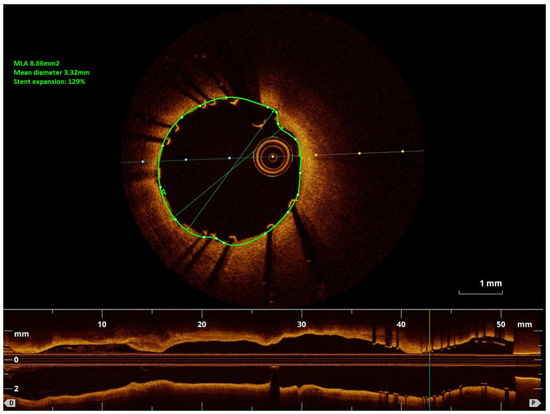

When performing revascularisation of a chronic total occlusion, contralateral injection is essential to visualise the distal bed of the occluded vessel, adding to procedural success. Here we describe a case of antegrade recanalisation of a left anter...